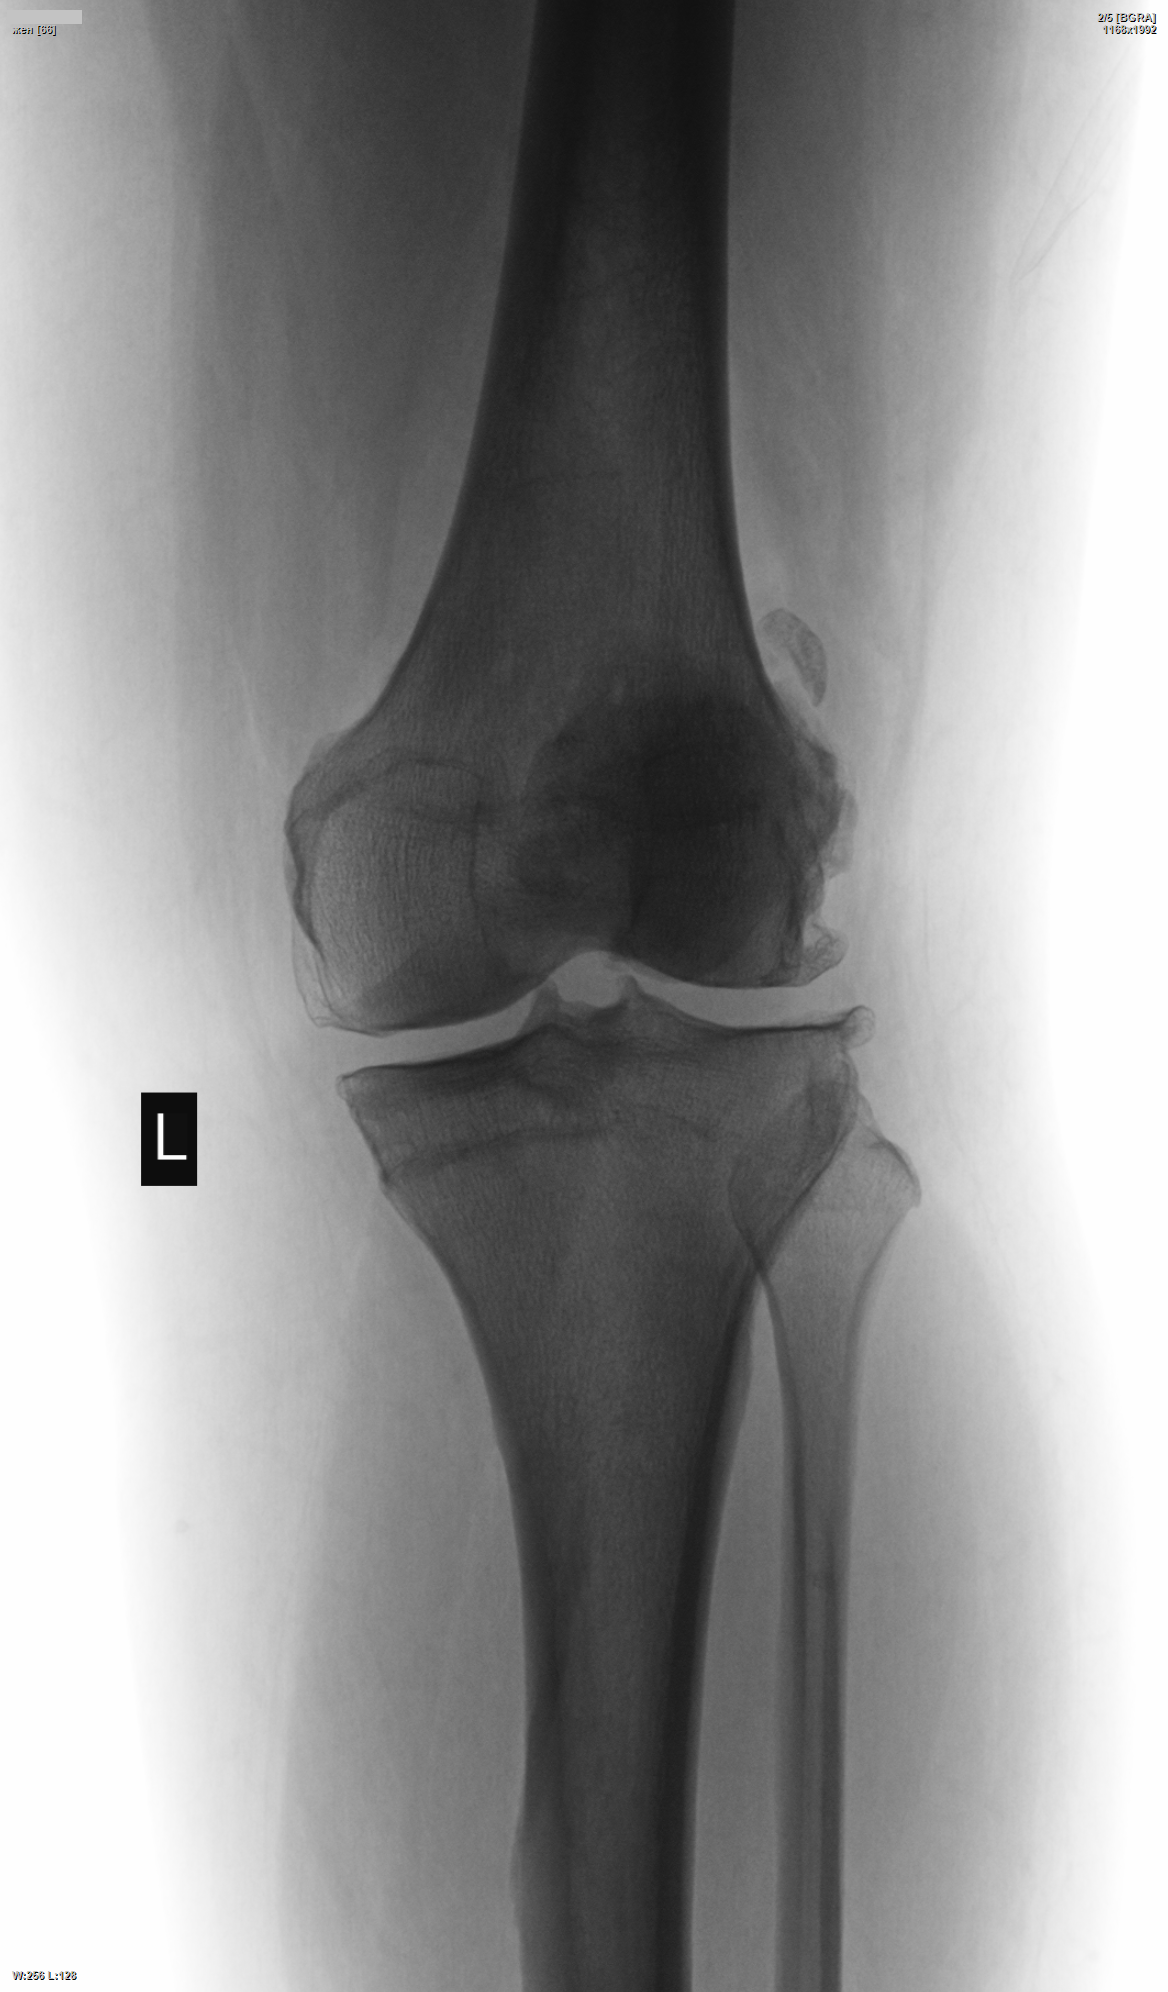

Женщина за 60 лет. Артрозом страдает давно. Как лечится не узнавал. Но в свете истории с "описанием снимков" и хондроматозом за 5 месяцев лечения артроза, решил показать. Кто что видит - на чём будем защиту строить? Или сразу УЗИ/МРТ предлагать?)

В левом коленном суставе "партиту" вижу. Хондромные тела в обоих суставах в наличии.По поводу фабелллы в правом коленном суставе посомневалась и решила хондроматозом ограничиться.

Артроз. Хондромные тела локализуются в заворотах суставной сумки.

Сан Саныч, а что я на снимках такое точками обвёл-начертил - что за тела такие? Локализация не та, но для кости не очень для того, что в суставе спрятался. И фабелла совсем хрящевая стала?.. Возраст всему виной или всё-таки что-то ещё помогло, подскажете, а?..

Никто, тут только артроз. Остальное - игра теней и воображения.